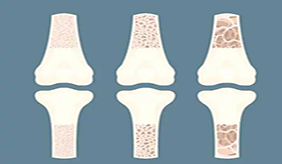

为什么骨质疏松症找上了年轻人呢? 除了包括种族、增龄、女性绝经、脆性骨折家族史等这些不可控的原因外,还有三个可控的原因: 1、不健康生活方式 体力活动少......